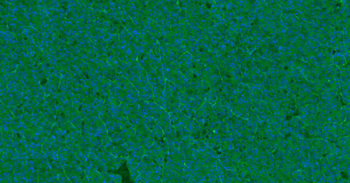

Immunofluorescense analysis of mouse lung tissue using anti-CD31 (primary antibody at 1:200)